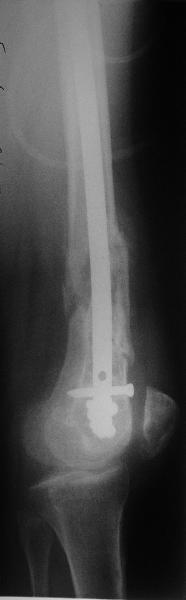

ПВ> Результат операции блокирующего остеосинтеза многооскольчатого перелома бедра.

По прямой проекции неплохо. Что за стержень?

Антеградный остеосинтез при дистальных переломах бедра мы применяем

давно, этот материал обобщен в канд. диссертации Александр

Виноградского.

Предприятие ЦИТО выпускает доработанные нами гвозди, которые хорошо

годятся для дистальных переломов, да и недороги. Можно вводть в

дистальное овальное отверстие 3 винта, которые заклинивают друг друга.

Большеберцовые стержни отлично выполняют роль ретроградных бедренных.

Конечно, которые не 9, а 12 мм в диаметре.